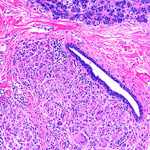

Duct ectasia with a central calcified keratin plug and associated giant cell inflammatory response

From the collection of Liron Pantanowitz, MD, Tufts University School of Medicine, MA